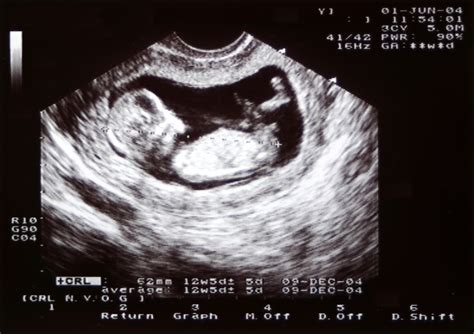

Gestational Age Confirming the due date by measuring the crown-rump length (CRL).

The 11 week ultrasound is typically performed either abdominally or transvaginally, depending on factors such as your body type and the position of the uterus. For most women at 11 weeks, an abdominal ultrasound is sufficient, where a transducer is moved over the belly with gel. However, if a clearer image is needed, a transvaginal approach may be used. The entire process is generally painless, though it can feel a bit cold due to the conductive gel.

During the appointment, the sonographer or doctor will focus on several key aspects to ensure the pregnancy is progressing as expected. They are not just looking for a heartbeat; they are assessing anatomical development and ensuring the pregnancy is located safely within the uterus. It is a moment of wonder for many, as you can often see the baby moving, though you may not feel those movements yet.

By the 11th week, your baby is roughly the size of a lime or a Brussels sprout, measuring about 1.5 to 2 inches long. Despite their small size, they are incredibly active. During the 11 week ultrasound, you might be surprised to see your baby performing various movements, such as curling their toes, stretching, or even hiccuping.